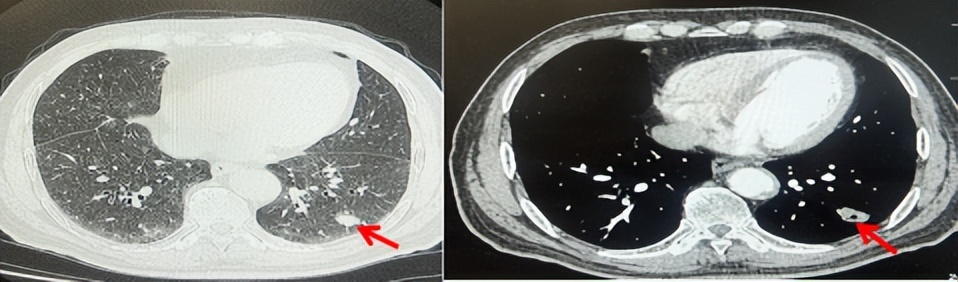

71岁男性,高血压病史20年,口服药物治疗,无糖尿病、心脏病等基础疾病,吸烟史50年,20支/天,已戒1年余,无饮酒史,无肿瘤家族史。2023.11因咳嗽、咳痰行胸CT检查:左肺下叶占位性病变,大小约12mmx8mm(如图5)。2023.11.20行“单孔胸腔镜左肺中下叶切除、肺门及纵隔淋巴结清扫、胸膜粘连松解术”;术后病理:(左肺下叶)结合免疫组化鳞状细胞癌(中、低分化),局部见脉管内癌栓,未见确切神经侵犯,(气管切缘)净。(淋巴结)未见转移癌0/19(4组0/1;5组0/1;6组0/2;7组0/1;9组0/1;10组0/2;11组0/3;12组0/2;13组0/2;14组0/4)。术后分期pT1bN0M0 IA期,术后定期复查。

图5:患者手术前(2023.11)胸部CT肺窗及纵隔窗